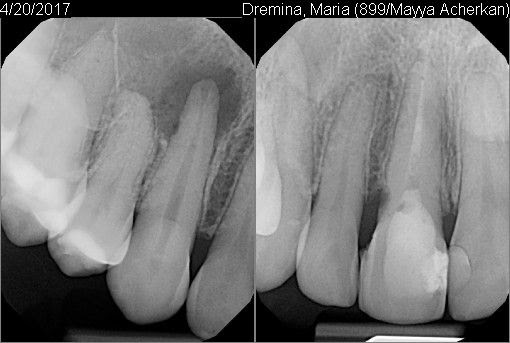

Мой сын случайно головой ударился о мой клык. Боли я почти не чувствовала, но со временем заметила шишечку на десне. Но не сразу придала значения, так как зуб полностью был здоров. Я не знала, что от такого незначительного удара корень зуба может умереть. Врач промыл канал, лекарство поставил всего на две недели, а потом закрыл канал. Чего я не ожидала, делала в другой стране. Шишка со щеки спала, но неожиданно через два почти месяца появилась вновь. За один день увеличилась и лопнула. Пришла к врачу, сделали снимок 3Д. По снимку видно, что уже кости нет. Инфекция распространилась ещё больше, как я понимаю, что уже захватывает соседний зуб. Мне предлагают сделать резекцию корня зуба. Понимаю, что альтернатива - это только удаление зуба. Так как живу в стране, где стоматология ужасно дорогая, и решается вопрос ехать в Россию, чтобы вылечить. Если есть, конечно, смысл.

Резекция верхушки корня может помочь в сохранении зуба, но думаю в связи с таким обширным воспалением зуб все же лучше удалить.

Соседний зуб пока можно попробовать пролечить, путём депульпирования и заведения лекарства за верхушку корня.